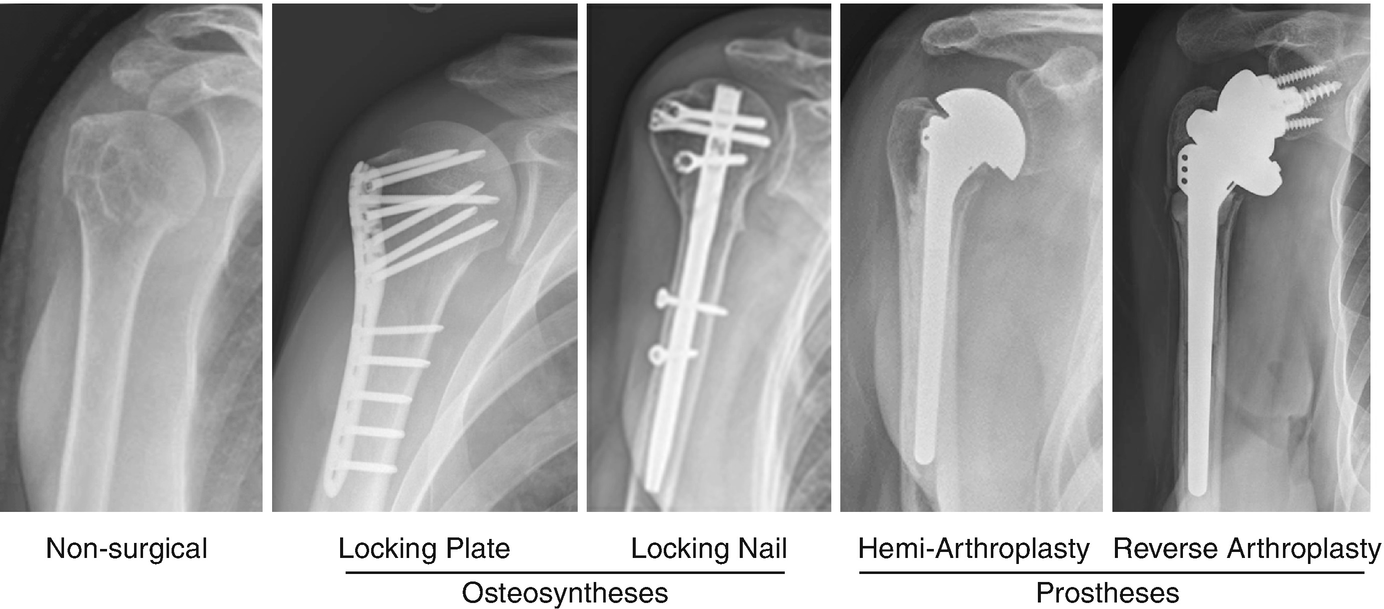

OTA Classification • 3 Main Types • Extraarticular fracture (13AX) • Partial articular fracture (13BX) • Complete articular fracture (13CX) • Each broad category further subdivided into 9 Proximal Humerus AO Classfication – www2aofoundationorg AO/OTA Classification Based on fracture location and the presence of impaction, angulation, translation, comminution, or dislocation;